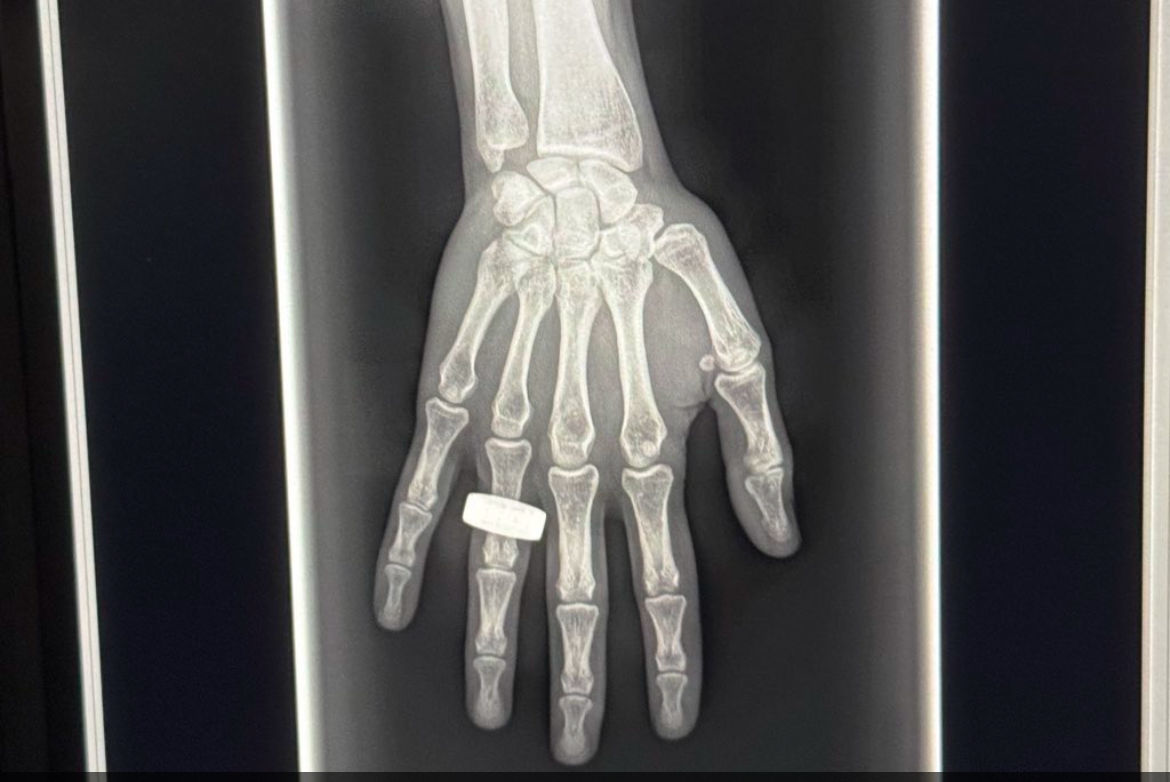

And while the hand x-ray acquired during the mission appears to prove the feasibility of using the technology in space, as well as perhaps validates the x-ray detector’s “spectral imaging” capabilities, the focus for ultraportable x-ray now returns to Earth, Cairnie said.